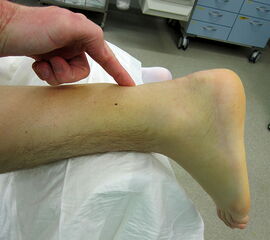

Abbildung 2

Der Thompson-Test 11 wird durch eine kräftige seitliche Wadenkompression mit der Hand ausgeführt und muss stets im Seitenvergleich erfolgen (Video 1). Die Nomenklatur des Thompson-Tests fällt je nach zitierter Literaturstelle unterschiedlich aus. In unserer Klinik zeigt ein positiver Thompson-Test eine Pathologie, eine Ruptur der Sehne an. Durch den häufig angelegten Muskulus plantaris fällt der Thompson-Test nicht immer vollständig positiv aus. In einigen Fällen lässt sich seine Sehne im Bereich der Rupturstelle palpieren. Ebenfalls können inkomplette Rupturen mit einem falsch negativen Befund imponieren (Abbildung). In unsicheren Situationen kann unterstützend ein leichter Druck mit den Fingern im Vorfußbereich die seitendifferente Kraftausübung beim Test aufzeigen.

Ergänzend kann der Matles-Test 12 durchgeführt werden. Der Patient flektiert in Bauchlage die Kniegelenke bis 90 Grad. Durch den fehlenden Gegenzug des Grastrocnemius-Soleus-Komplexes kommt es auf der betroffenen Seite zu einer verstärkten Dorsalextension im Sprunggelenk. Auch dieser Test kann durch einen vorhandenen Muskulus plantaris oder durch eine Partialruptur verfälscht werden.